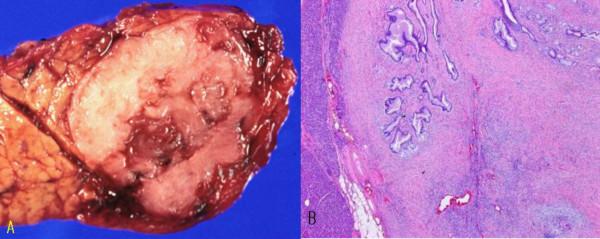

胰腺黏液性囊腺瘤,以形成实性肿瘤的间质为主。

Mucinous cystadenoma of the pancreas with predominant stroma creating a solid tumor.

A 51-year-old female presented with a pancreatic mass incidentally found on the abdominal computed tomography. She underwent distal pancreatectomy. The sectioned surface of the pancreas revealed a circumscribed, whitish gray ovoid firm mass with some cystic spaces. Microscopically, glandular or small cystic structures were scattered in the predominant stroma creating a solid appearance. The subepithelial stromal component was composed of cytologically bland looking spindle cells, which resembled ovarian stroma. The stromal cells were reactive to CD 34, vimentin, progesterone receptor and calretinin. The microscopy was consistent with mucinous cystadenoma of the pancreas.

一名51岁女性因腹部计算机断层扫描偶然发现胰腺肿物。她接受了胰腺远端切除术。胰腺的切面显示有一个边界清楚、灰白色卵圆形坚实肿物,伴有一些囊腔。显微镜下,腺管或小囊状结构散在于主要的间质中,形成实性外观。上皮下间质成分由细胞学表现温和的梭形细胞组成,类似卵巢间质。间质细胞对CD 34、波形蛋白、孕激素受体和钙视网膜蛋白呈阳性反应。显微镜检查结果符合胰腺黏液性囊腺瘤。